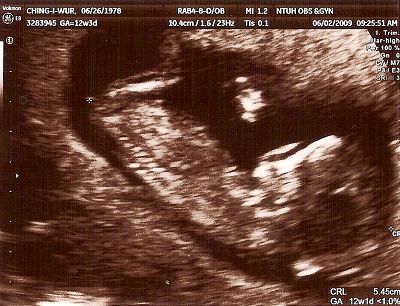

12W2D醫生安排照頸部透明帶

老愛趴著的娃娃,讓我只得在醫院長長的走廊來回不停地走

一直不斷跟他溝通快快轉過來

好不容易可以照了

醫生帶著我數著娃娃的手指頭,1、2、3、4、5

看看四肢、心臟 、屁屁等器官

看著娃娃揮舞著四肢可愛的模樣,好感動好感動

隨著時間的經過,大概也有三十分鐘了吧!

醫生左搖右晃地還沒結束

心中正納悶著

結果醫生說鼻骨好像不是很清楚

有百分之六十的唐寶寶有這個情況

頓時,心都涼了一截

在醫生的說明下,叫我別太擔心,因為還要看抽血及整體的評估報告

拿了超音波照片的我,帶著一顆忐忑不安的心離開醫院